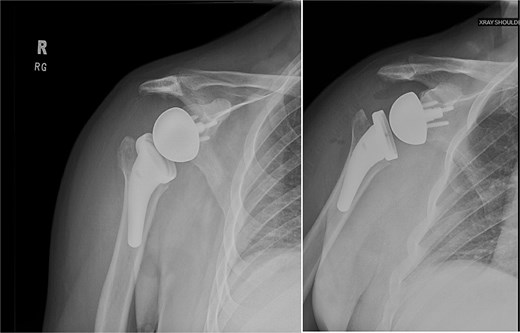

Both shoulders were reduced urgently by the orthopedic team, with immediate improvement in paresthesias (Fig. 2). Post-reduction CTs were significant for bilateral chronic rotator cuff disease with superior migration of the humeral heads, right-sided supraspinatus and subscapularis atrophy, and a left nondisplaced glenoid fracture (Figs 3 and 4). He was discharged home in bilateral slings.

Post-reduction X-rays demonstrating congruency restored to right and left glenohumeral joints, with evidence of superior humeral head migration bilaterally.